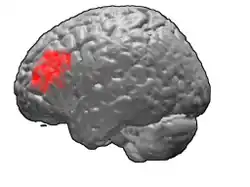

Image

Lateral view.

Brodmann area 46, or BA46, is part of the frontal cortex in the human brain. It is between BA10 and BA45.

BA46 is known as middle frontal area 46. In the human brain it occupies approximately the middle third of the middle frontal gyrus and the most rostral portion of the inferior frontal gyrus. Brodmann area 46 roughly corresponds with the dorsolateral prefrontal cortex (DLPFC), although the borders of area 46 are based on cytoarchitecture rather than function. The DLPFC also encompasses part of granular frontal area 9, directly adjacent on the dorsal surface of the cortex.